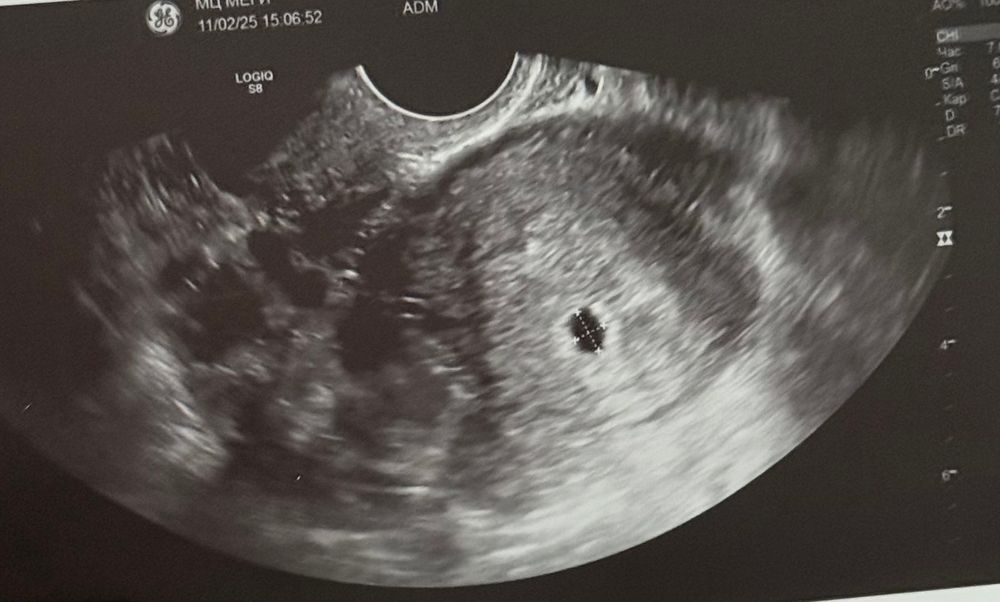

Всем привет, кто разбирается, все ли хорошо по узи? Переживаю за кисту в яичнике

пчела → Зачатие УЗИ жду мальчика, 7 неделя Омск первое узи Всем привет, кто разбирается, все ли хорошо по узи? Переживаю за кисту в яичнике Посмотрите еще 20 записей на эту тему Святая инквизиция Мама мальчика (4 года) Нур-Султан (Астана) Все хорошо) киста тоже норма в своем роде. Пусть хорошо питает беременность раз такая крутая)🍀 0 12.02.2025 Ответить пчела Мама мальчика (7 месяцев) Омск Karmilla, спасибо ☺️ 0 12.02.2025 Ответить Узи ВМИ и проверка проходимости труб Похожие записи А я тут первый раз!!!! Каковы первые признаки беременности? Первое УЗИ... я первый раз тут.. Первый протокол Чаты Беременных Выберите чат: Июлята-2026 Августята-2026 Сентябрята-2026 Октябрята-2026 Ноябрята-2026 Декабрята-2026